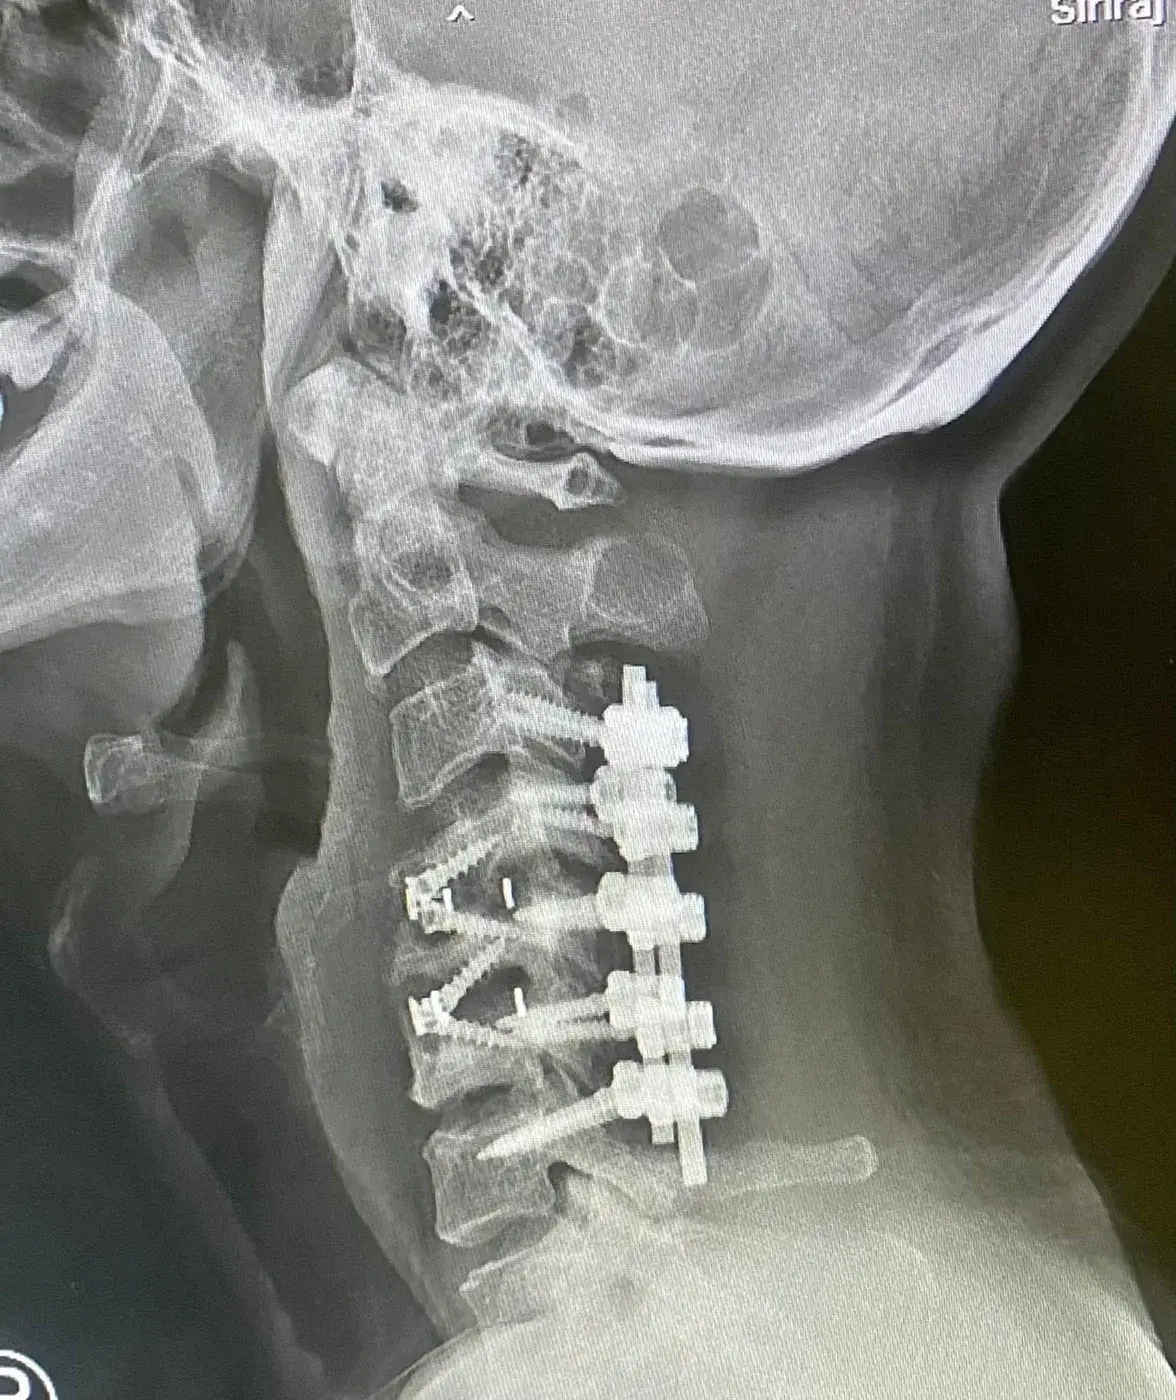

โทนเล่าว่า ก่อนหน้านี้เขาเคยเชื่อว่า ตัวเองสุขภาพแข็งแรง ไม่จำเป็นต้องซื้อประกัน เพราะยังหนุ่มแน่น ไม่ป่วยง่าย และหากป่วยจริง ๆ ก็ยังมี บัตรทอง 30 บาทรักษาทุกโรค อยู่แล้ว แต่ความคิดทั้งหมดเปลี่ยนไป เมื่อวันหนึ่งเขาตรวจพบว่าเป็น “โรคหมอนรองกระดูกที่คอเคลื่อนกดทับเส้นประสาท” ซึ่งมักเกิดในผู้สูงอายุ แต่กลับเกิดขึ้นกับเขาในวัยยังไม่ถึงกลางคน

โรคนี้ทำให้เขาต้องเข้ารับการ ผ่าตัดถึง 3 ครั้ง รวมค่าใช้จ่ายกว่า 3 ล้านบาท

รอบที่ 1: ผ่าตัดครั้งแรก ค่ารักษาเกิน 1 ล้านบาท

รอบที่ 2: อาการยังไม่ดีขึ้น ต้องผ่าซ้ำอีกครั้ง

รอบที่ 3: ผ่าตัดใหญ่ครั้งสุดท้ายที่โรงพยาบาลศิริราช ปิยมหาราชการุณย์ ใช้เวลาผ่าตัดกว่า 6 ชั่วโมง และต้องพัก ICU อีก 2 วัน